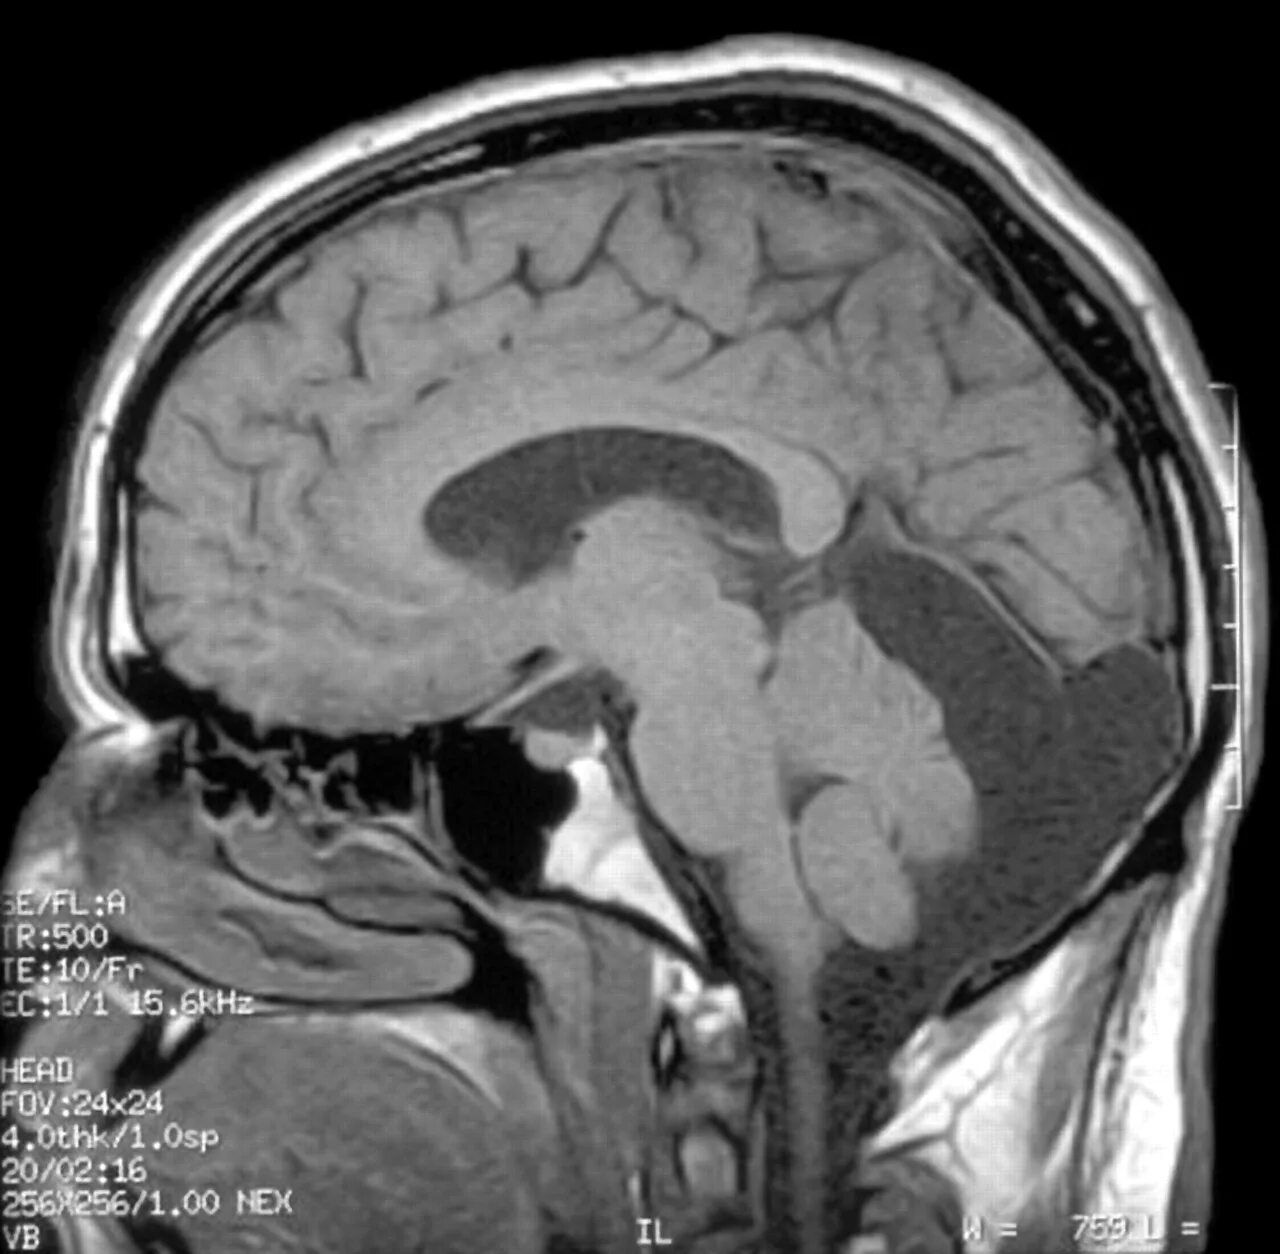

Денди уокера мрт